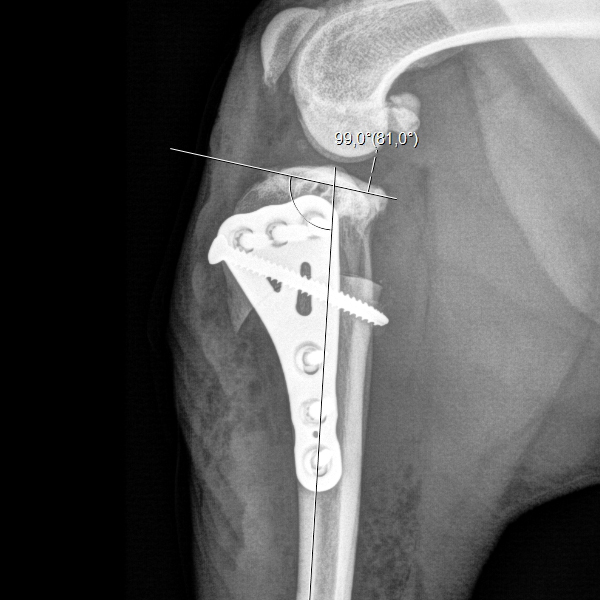

Case Description: The patient is a 35 kg dog. Following the motto "go big, go strong", a LeiLOX CBLO 3.5 mm broad plate was used for this case.

Thank you, Dr. Schmökel for sharing this case with us!

Dr. HUGO SCHMÖKEL (DVM, PhD, Dipl.ECVS, MRCVS) said:

“The X-Ray was taken 4 weeks post-op. The patient is practically lame-free.”